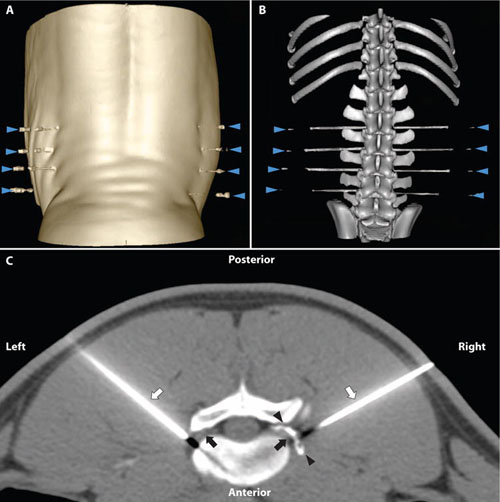

- Polvoy P, Seo Y, Parker M, Stewart M, Siddiqua K, Manasca HS, Ravanfar V, Blecha J, Hope TA, Vanbrocklin H, Flavell R, Barry J, Hansen E, Villanueva-Neyer J, Engel J, Rosenberg OS, Wilson DM*, Ohliger MA*. Imaging joint infections using D-methyl-11C methionine PET/MRI: initial experience in humans (2022). EJNMMI

The Wilson laboratory is pursuing clinically translatable biomarkers for infection, particularly discitis-osteomyelitis, which may be difficult to diagnose using computed tomography (CT) and magnetic resonance imaging (MRI). Existing clinical strategies to image bacterial infection in patients rely on activated immune cells (either 111In white blood-cell scan or 18F-FDG) and thus cannot reliably distinguish living bacteria from sterile inflammation. We are studying translational biomarkers for hyperpolarized 13C spectroscopy and positron emission tomography (PET) that target metabolic pathways specific to bacteria. We have developed several agents with excellent clinical promise including D-amino acid derived tracers (collaborative work with co-PI’s Michael Ohliger and Oren Rosenberg). More recently we have developed imaging tools to detect the suppression of ACE2, the primary receptor for SARS-CoV-2 entry, in COVID-19.